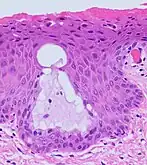

Transformation zone mucosa, when the squamocolumnar junction has a gradual transition. It consists of a mix of stratified squamous epithelium and mucinous glands. H&E stain.

Nabothian cysts (or Nabothian follicles) form in the transformation zone where the lining of metaplastic epithelium has replaced mucous epithelium and caused a strangulation of the outlet of some of the mucous glands.[17]:410–411 A buildup of mucus in the glands forms Nabothian cysts, usually less than about 5 mm (0.20 in) in diameter,[4] which are considered physiological rather than pathological.[17]:411 Both gland openings and Nabothian cysts are helpful to identify the transformation zone.[15]:106